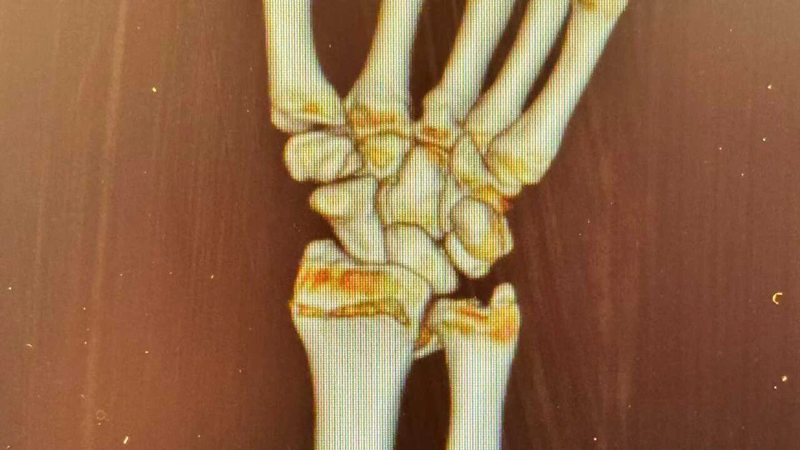

骨外科:无影灯下,为生命“守岁”的工匠

对于骨外科而言,春节假期往往是意外伤害的高发期。为了能让患者尽早解除痛苦、早日回家团圆,骨外科的团队选择了与患者为伴。

农历正月初五,当大家还在走亲访友时,骨外科医生李刚已完成了两例摔伤患者的救治工作。“大过年的,能早一点救治就早一点救治,让他们好好过年。”这是李刚医生朴素的心声,也是全体骨科医护人员的承诺。无影灯下,他们专注的眼神是对生命最大的尊重。

洗菜摔伤治疗前后对比

厕所摔伤治疗前后对比